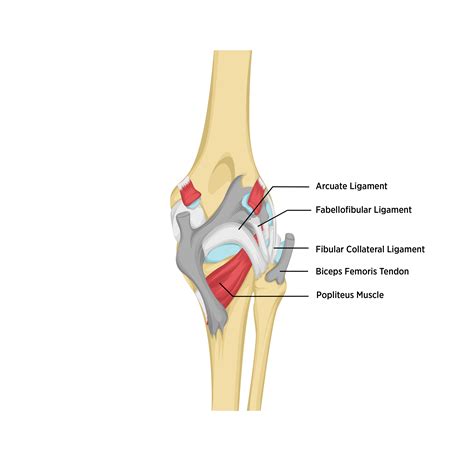

The posterolateral aspect of the knee is a sophisticated region composed of static and dynamic stabilizers. Understanding how these structures function together is essential to comprehending the mechanics of a Posterolateral Corner Injury. The main static stabilizers include:

• Lateral Collateral Ligament (LCL): The primary restraint against varus stress.

• Popliteus Tendon: Acts as a key stabilizer against external tibial rotation.

• Popliteofibular Ligament: Works in concert with the popliteus tendon for rotational stability.

• Arcuate Ligament Complex: Provides structural support to the posterior capsule.

Dynamic stabilizers, including the lateral head of the gastrocnemius muscle, the biceps femoris tendon, and the iliotibial band, also contribute to the overall tension of the knee joint. When these components are damaged, the joint loses its ability to track correctly, leading to functional instability and long-term risk of degenerative joint disease.